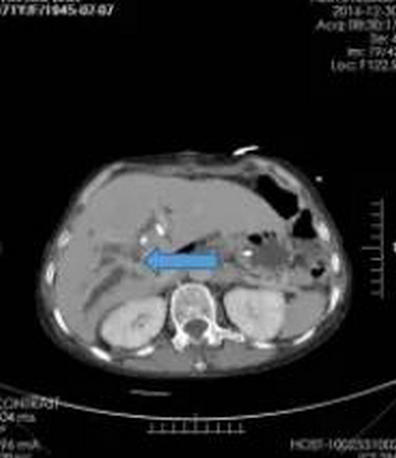

纳米刀消融术后1周SCT增强扫描(箭头所指为原肿瘤部位)